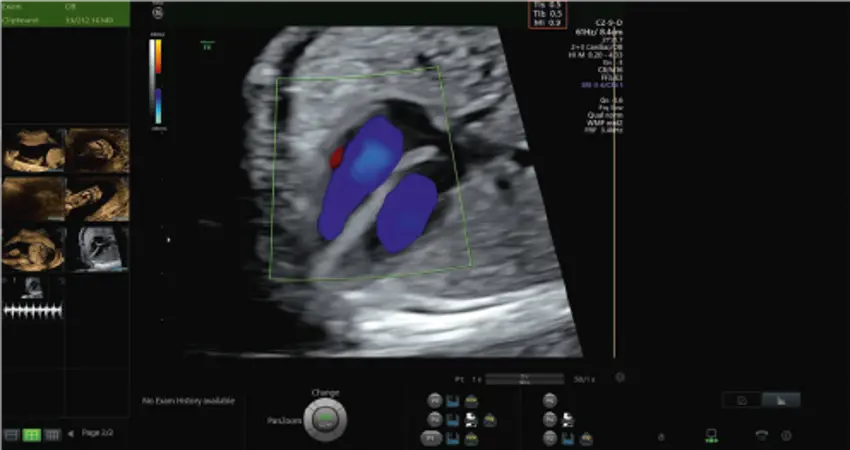

A frame recorded during a routine ultrasound scan. The safety markers are displayed in the top-right of the ultrasound image.

The study uses automated analysis on videos of ultrasound scans where eye-tracking data on the operator of the ultrasound was recorded. This is a huge improvement on previous studies where still images and short loops are mainly used instead of video, and this is the only study to have video information for all stages of pregnancy. They were able to look at how often sonographers and doctors checked safety measures such as the Thermal Index (TI) Value during 637 ultrasound scans in the first, second and third trimesters of pregnancy. The TI Value gives an estimate of the risk, from thermal load, associated with the ultrasound beam – if the TI value is kept under a set limit, then ultrasound can be used for a longer period. If TI limit values are surpassed, examination time must decrease.